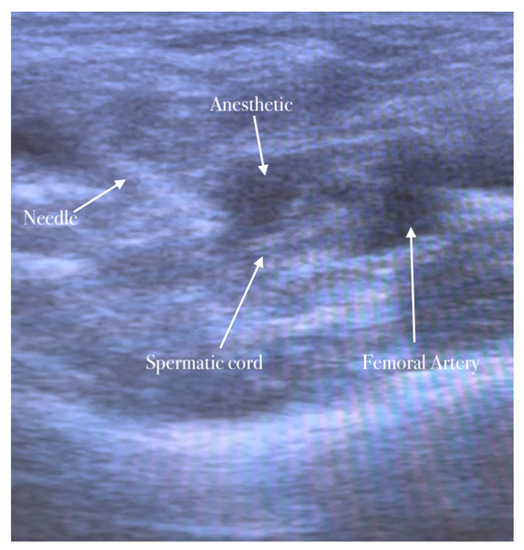

5.3. Genitofemoral Nerve Block

The second step of anesthesia consists of the genitofemoral nerve block. The genitofemoral nerve block decreases the pain induced by the traction of the hernia sac and improves the quality of analgesia for surgery in the inguinal region. The procedure is similar to the ilioinguinal–iliohypogastric nerves block. The genitofemoral nerve is formed from the first and second ventral rami of the lumbar nerve. It emerges on the anterior surface of the psoas major along the medial border, descends on the psoas major within the fascia iliaca, and crosses the posterior to the ureter and peritoneum. The nerve follows the lateral border of the common and external iliac artery. It is divided into genital and femoral branches above the inguinal ligament. The genital branch of the genitofemoral nerve passes through the transversalis and spermatic fascia before it enters the deep inguinal ring. It lies immediately laterally or deeply in the spermatic cord/round ligament and supplies the cremaster muscle [16,17].

The high-frequency linear probe is initially kept perpendicular to the inguinal ligament just above the femoral vessels. The final position of the probe is about 2 cm lateral to the pubic tubercle. In this position, the femoral artery is identified. The inguinal canal lies above and medially the femoral artery appearing as an oval or circular structure. The probe is then moved slightly in the medial direction away from the femoral artery.

The needle is inserted in the plane in a medial-to-lateral direction; 10 mL of anesthetic is injected in the transversus abdominis plane, as seen in Figure 5, Figure 6 and Figure 7.

Spermatic cord identification.

The anesthetic is injected in the spermatic cord.